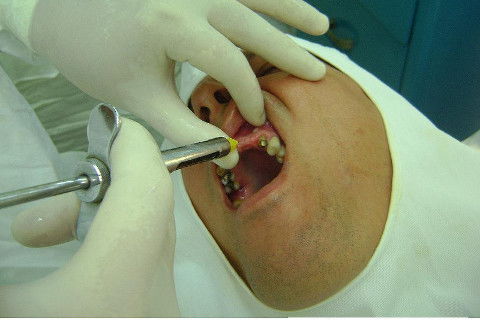

Cirurgia realizada hoje de manhã...No planejamento percebi medindo espessura do rebordo com especímetro que as medidas não estavam muito boas, ou o ideal, em torno de 4,5 a 5 mm ate´o terço médio do rebordo e melhorava no final, com 6 a 7 mm. Optei então por uma pequena expansão usando os expansores rosqueáveis. Aconteceu uma pequena fenestração na hora da fixação dos implantes, especialmente na região do 22 que fraturou o início da tábua óssea, mas não me preocupei porque não foi mais do que 2 mm de fratura em direção apical, o implante ficou infraósseo e com boa estabilidade (60 N no 21 e 40 N no 22). Esta fratura tb não deixou osso completamente solto, foi do tipo galho verde, deixei em posição e suturei normalmente. Só não fiz e nem estava planejado carga imediata mesmo, mais pelo motivo da oclusão inadequada do caso.

Fotos do caso